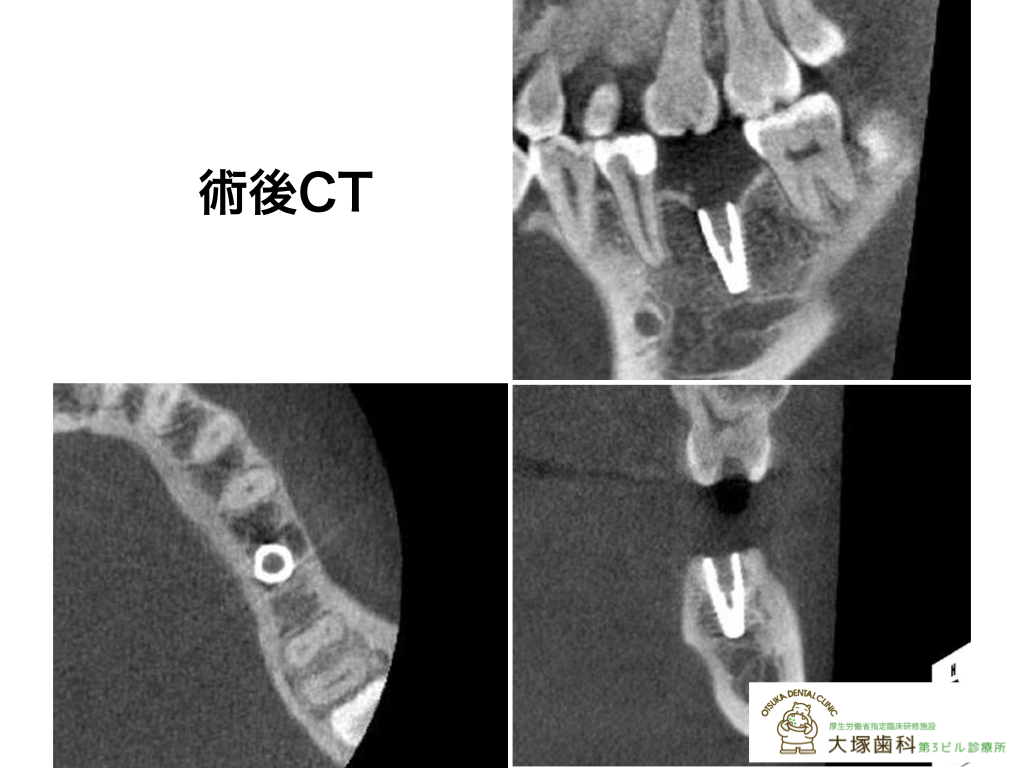

[レントゲン術前]

[レントゲン術後]